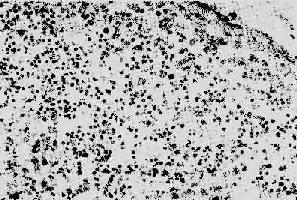

图4-15 AIDS淋巴结 淋巴细胞明显减少,无淋巴滤泡及副皮质区之分

图4-14 HIV侵犯TH细胞后免疫调节障碍示意图 【病变】 病变可归纳为全身淋巴样组织的变化,机会性感染和恶性肿瘤三个方面。 1.淋巴样组织的变化早期及中期,淋巴结肿大。镜下,最初有淋巴滤泡明显增生,生发中心活跃,髓质出现较多浆细胞。随后滤泡的外套层淋巴细胞减少或消失,小血管增生,并有纤维蛋白样物质或玻璃样物质沉积,生发中心被零落分割。副皮质区的淋巴细胞(CD4+细胞)进行性减少,代之以浆细胞浸润。晚期的淋巴结病变,往往尸检时才能看到,呈现一片荒芜,淋巴细胞,包括T、B细胞几乎均消失殆尽,无淋巴滤泡及副皮质区之分,仅有一些巨噬细胞和浆细胞残留(图4-15)。有时特殊染色可显现大量分枝杆菌、真菌等病原微生物,却很少见到肉芽肿形成等细胞免疫反应性病变。 AIDS病人的脾呈轻度肿大,镜下有淤血,T、B细胞均减少,淋巴滤泡及淋巴鞘缺如。死于感染的病例,脾内常有较多中性粒细胞及一些吞噬病原微生物的巨噬细胞。扁桃体、小肠、阑尾和结肠内的淋巴样组织均萎缩,淋巴细胞明显减少。胸腺的组织与同龄人相比,呈现过早萎缩,淋巴细胞减少、胸腺小体钙化。 2.继发性感染多发性机会感染是本病另一特点,感染的范围广泛,可累及各器官,其中以中枢神经系统、肺、消化道的疾病最为常见。病原种类繁多,一般可有二种以上感染同时存在。由于严重的免疫缺陷,感染所致之炎症反应往往轻而不典型。如肺部结核菌感染,很少形成典型的肉芽肿性病变,而病灶中的结核杆菌却甚多。 约有半数病例有卡氏肺孢子虫感染,因之对诊断本病有一定参考价值。病变区肺间质及肺泡腔内有较多巨噬细胞及浆细胞浸润,其特征性变化是肺泡腔内出现由大量免疫球蛋白及原虫组成的伊红色泡沫样渗出物。 约70%的病例有中枢神经系统受累,其中继发性机会感染有播散性弓形虫或新型隐球菌(cryptococcus neoformans)感染所致的脑炎或脑膜炎;巨细胞病毒和乳多空病毒(papovavirus)所致的进行性多灶性白质脑病等。由HIV直接引起的疾病有脑膜炎、亚急性脑病、痴呆等。这一情况提示,除淋巴细胞、巨噬细胞外,神经系统也是HIV感染的靶组织。 3.恶性肿瘤 约有30%患者可发生Kaposi肉瘤。该肿瘤为血管内皮起源,广泛累及皮肤、粘膜及内脏,以下肢最为多见。肉眼观肿瘤呈暗蓝色或紫棕色结节。镜下显示成片梭形肿瘤细胞,构成毛细血管样空隙,其中可见红细胞。与典型的Kaposi肉瘤不同之处在于其多灶性生长和进行性临床过程。其他常见的伴发肿瘤包括未分化性非何杰金淋巴瘤、何杰金和Burkitt淋巴瘤等,脑原发性淋巴瘤也很常见。 【临床病理联系】 临床上将AIDS的病程分为三个阶段:①早期或称急性期,感染病毒3~6周后可出现咽痛、发热、肌肉酸痛等一些非特异性表现。病毒在体内复制,但由于患者尚有较好的免疫反应能力,2~3周后这种急性感染症状可自行缓解;②中期或称慢性期,机体的免疫功能与病毒之间处于相互抗衡阶段,在某些病例此期可长达数年或不再进入末期。此期病毒复制持续于低水平,临床可以无明显症状或出现明显的全身淋巴结肿大,常伴发热、乏力、皮疹等;③后期或称危险期,机体免疫功能全面崩溃,病人持续发热、乏力、消瘦、腹泻,并出现神经系统症状,明显的机会感染及恶性肿瘤,血液化验可见淋巴细胞明显减少(<30%),CD4+细胞减少尤为显著,CD4+细胞与CD8+细胞之比可由原来的2下降至0.5以下,细胞免疫反应丧失殆尽。 本病的预后差,死亡率达100%,致病原因虽已清楚,但制备有效的疫苗尚有待时日,其困难在于HIV在不同的患者有惊人的多型性,目前又无理想的治疗药物,因此大力开展预防,对防止AIDS流行至关重要。